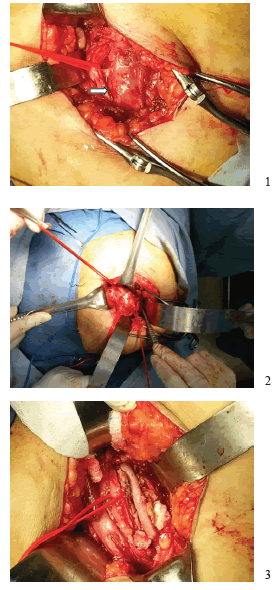

Fue sometida a cirugía: por la vía A (en decúbito supino), se extrajo el injerto de la safena mayor en el muslo derecho; por la vía B (en prono), se hizo una incisión oblicua en el glúteo derecho, se hizo la disección por planos y de las fibras del músculo glúteo mayor, exponiendo las venas glúteas y el nervio ciático superpuestos y adheridos al aneurisma de la arteria ciática persistente. Se liberó el nervio y se ligó la vena. La arteria se disecó y reparó en sus porciones, proximal y distal al aneurisma.

Se administró una dosis intravenosa de 6.000 UI de heparina no fraccionada, y se procedió al pinzamiento y la apertura longitudinal del aneurisma, la extracción de los trombos y la reconstrucción con el injerto de safena invertida (figura 3). Al final de la cirugía, se confirmó la presencia del pulso poplíteo derecho, con buena intensidad.